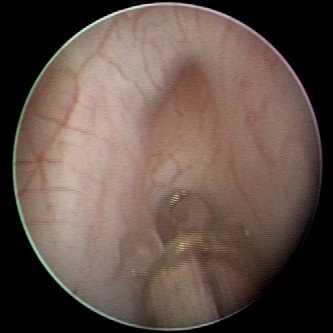

Суть эндоскопической коррекции рефлюкса заключается в восстановлении нарушенной антирефлюксной функции мочеточника путем введения под его выходной отдел жидкого инертного полимера. Полимер формирует бугорок, который после застывания служит жесткой опорой для мочеточника, верхняя стенка которого, плотно прилегая к нижней, обеспечивает клапанную антирефлюксную функцию (рис. 2).